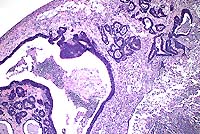

Case 5-1. Colon. Shows subserosal, colonic adenocarcinoma with cyst and abscess formation. 4X

AFIP Diagnosis: Colon: Adenocarcinoma, colonic, Long-Evans rat, rodent.

Conference Note: There was considerable variation in the slides distributed for this case. Several slides viewed in conference demonstrated minimal or no invasion of neoplastic cells into the tunica muscularis, and no neoplastic cells were present in the subserosal abscess. This led some participants to a diagnosis of atypical hyperplasia or carcinoma in situ. However, in other slides, invasive growth indicative of malignancy is evident.